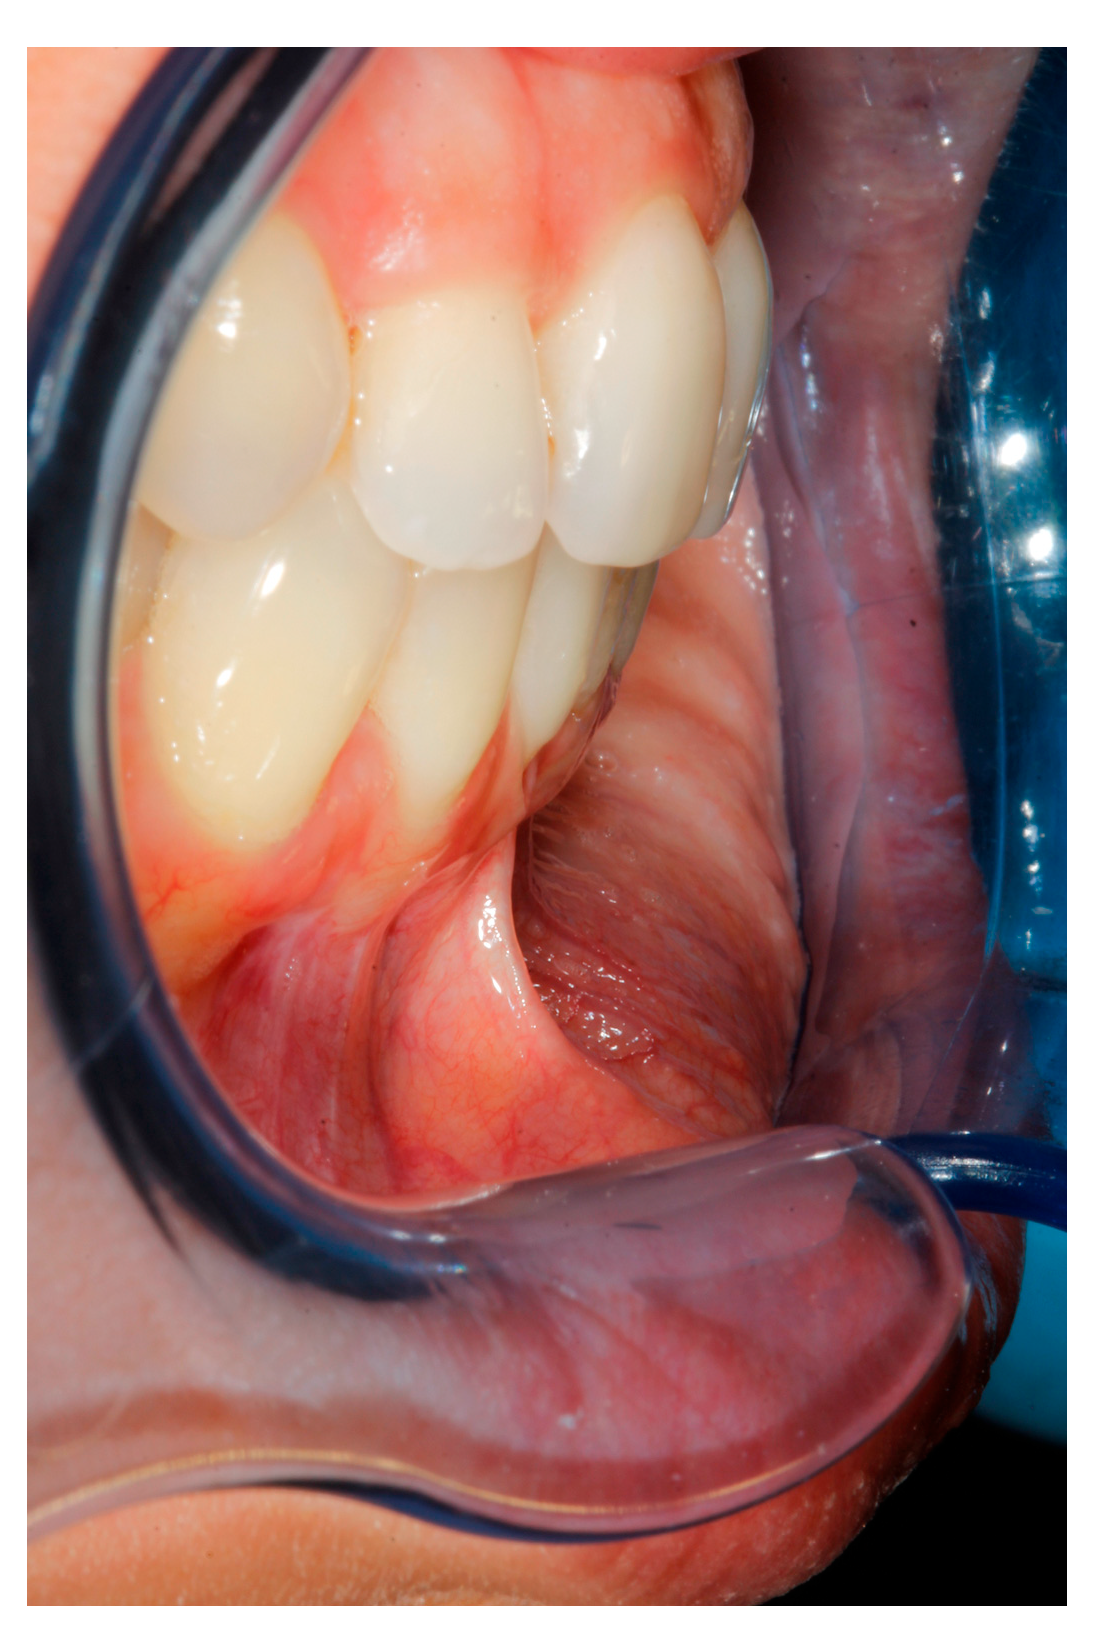

- (a)

- deep partial thickness incision (blade parallel to the periosteum) made at the level of the external insertion of the frenulum;

- (b)

- elimination of superficial mucous tissue and muscle of the frenulum;

- (c)

- a series of detached points with periosteal anchorage for the apical positioning of the lining mucosa of the lip and the second intention healing of the exposed periosteum.